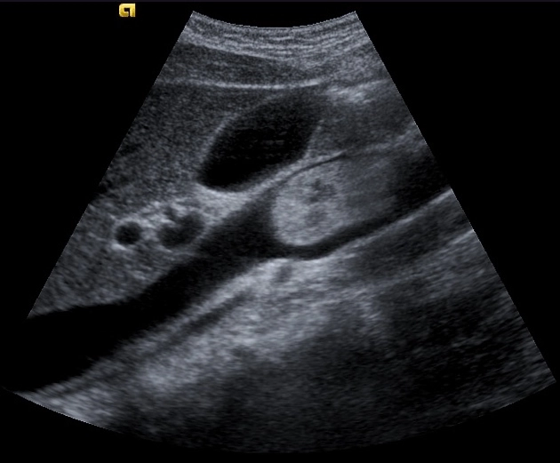

<p>In this sagittal plane, what is this structure?</p>

In this sagittal plane, what is this structure?

Aorta

IVC

<p>What is this structure in this the picture?</p>

What is this structure in this the picture?

Celiac Trunk

<p>What is this structure?</p>

What is this structure?

Aorta with the SMA coming off the top